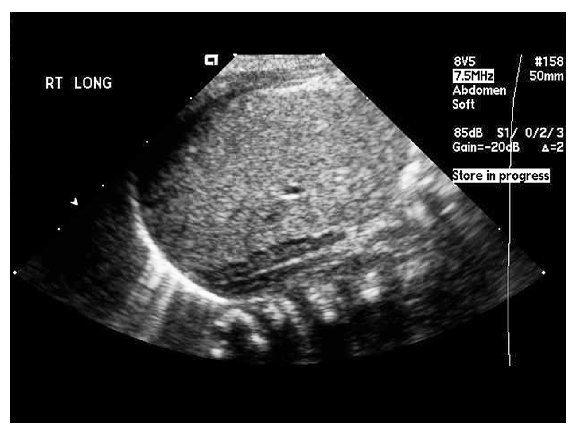

Fig. 2. Fosa renal derecha: nótese la alteración morfológica de la glándula suprarrenal derecha (straight adrenal) condicionada por la ausencia del riñón derecho.